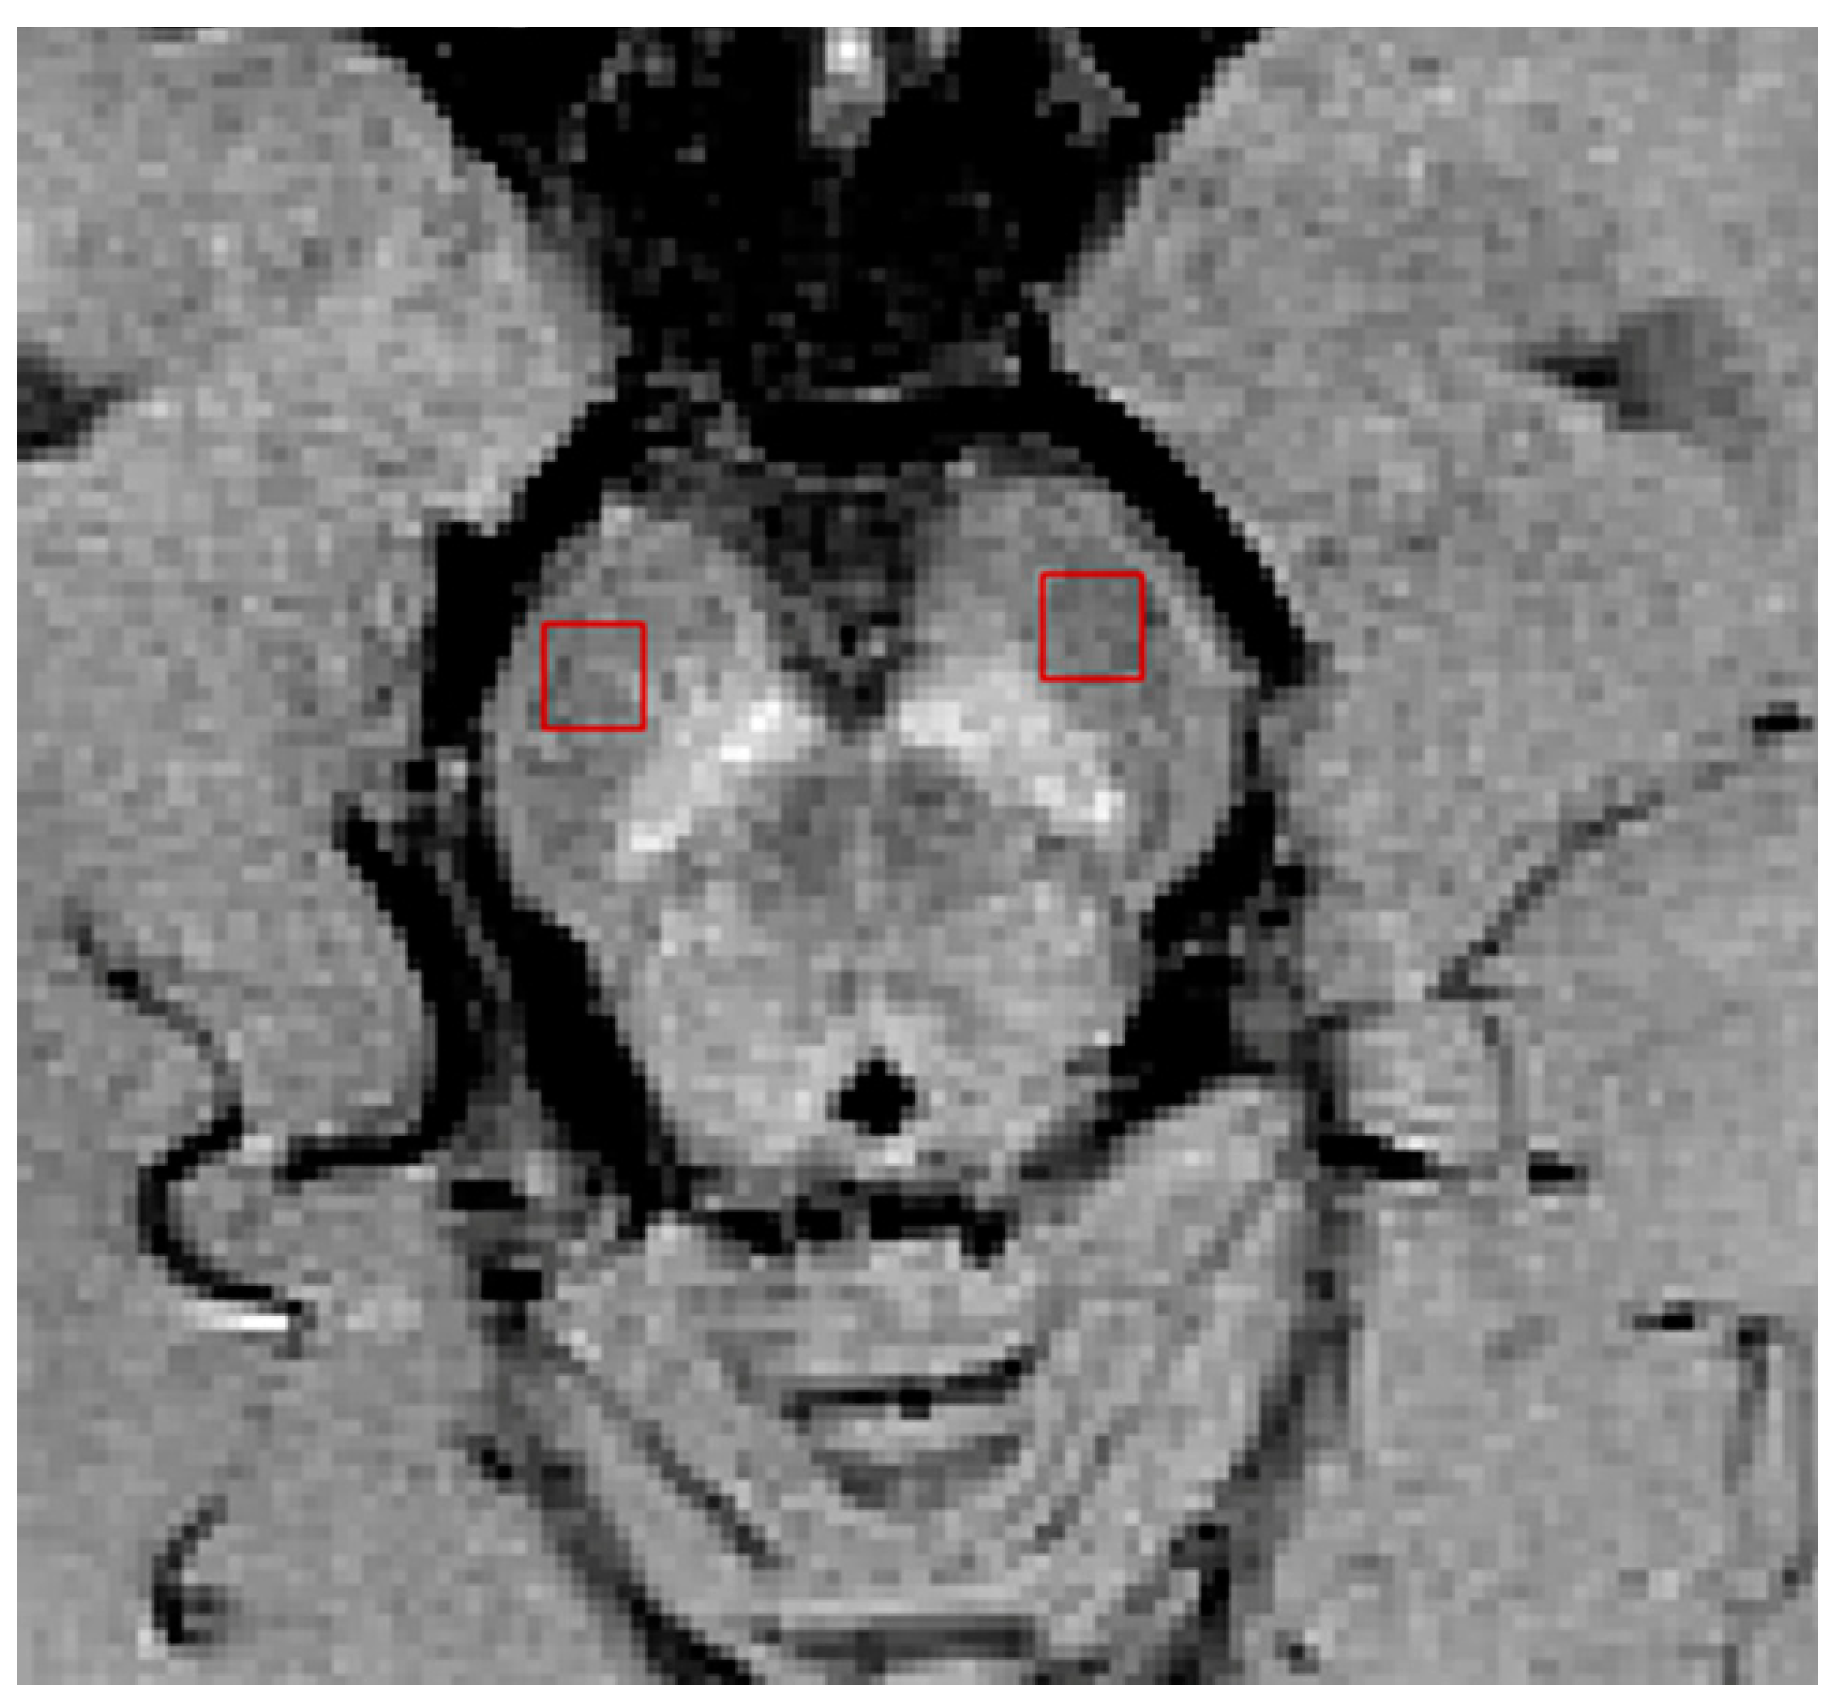

2.2. Imaging Protocols

2.3. Imaging Data Analyses